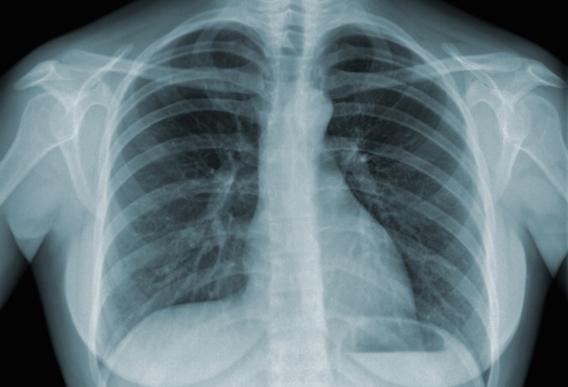

Poumon : fumer un paquet par jour engendre 150 mutations génétiques

Le fait de fumer un paquet de cigarettes par jour est associé à 150 mutations génétiques des cellules pulmonaires, du larynx, de la bouche et de la vessie.

L’étude a de quoi conforter dans leur idée tous ceux qui viennent de se lancer dans le Moi(s) sans tabac… Le fait de fumer un paquet par jour serait associé à au moins 150 mutations par an dans les cellules pulmonaires, selon des travaux publiés dans la revue Science.

Si le plus grand nombre de mutations génétiques provoquées par le tabac a été observé dans les tissus pulmonaires, d'autres parties de l'organisme portent aussi la signature de ces altérations de l'ADN, précisent les chercheurs. Cela pourrait expliquer pourquoi et comment le fait de fumer provoque différents types de cancer (poumon, bouche, larynx, pharynx, œsophage, foie, pancréas, sein...).

Pour cette première analyse étendue de l'ADN cancéreuse liée au tabac, ces chercheurs ont scruté 5 243 génomes, représentant treize localisations de cancers potentiellement favorisés par le tabagisme. Ils ont comparé les cancers de fumeurs avec des cancers similaires de personnes n'ayant jamais fumé.

Dans les autres organes, l'étude révèle qu'un paquet de cigarettes par jour entraîne en moyenne 97 mutations de plus par an dans l'ADN du larynx, 39 dans le pharynx, 23 dans la bouche, 18 dans la vessie et 6 dans le foie.